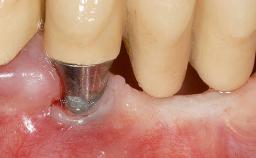

Adequate peri-implant soft-tissue thickness is essential not only for esthetic but also for functional reasons. In this case, Vincenzo Iorio Siciliano demonstrates how he achieved increased height and thickness of posterior peri-implant soft tissues to obtain a stable mucosal seal and a width of keratinized tissue favorable to toothbrushing.

The patient, a healthy 38-year-old woman, was referred for increasing the width of the keratinized tissues at the buccal aspect of dental implant 46. The site exhibited a premature-closure screw exposure caused by trauma during chewing, with inadequate keratinized tissue.